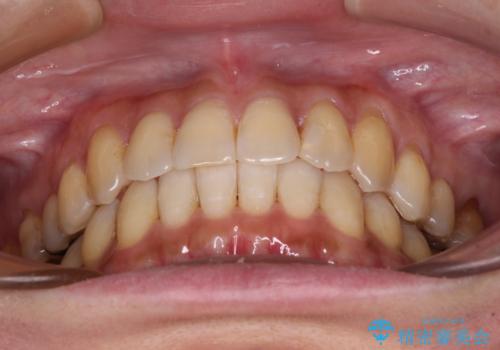

- 前歯のクロスバイトが気になり、インビザラインによる矯正治療を希望して来院された患者様です。

上顎側切歯(上の真ん中から2番目の歯)が舌側転位している場合、インビザラインでは仕上げきれないことが多く、更には無理して動かそうとすると歯髄壊死を起こすリスクが高いと言われています。

インビザラインで歯列を移動する前に、上顎前歯をワイヤー矯正で整え、その後上下歯列をインビザラインにて矯正治療を行うこととしました。

舌側転位している側切歯特有の、切縁の位置が不揃いであったり、根元が内側に引っ込んだ状態であったりという、インビザライン独特の仕上がりになることなく、きれいに整った歯列とすることができました。